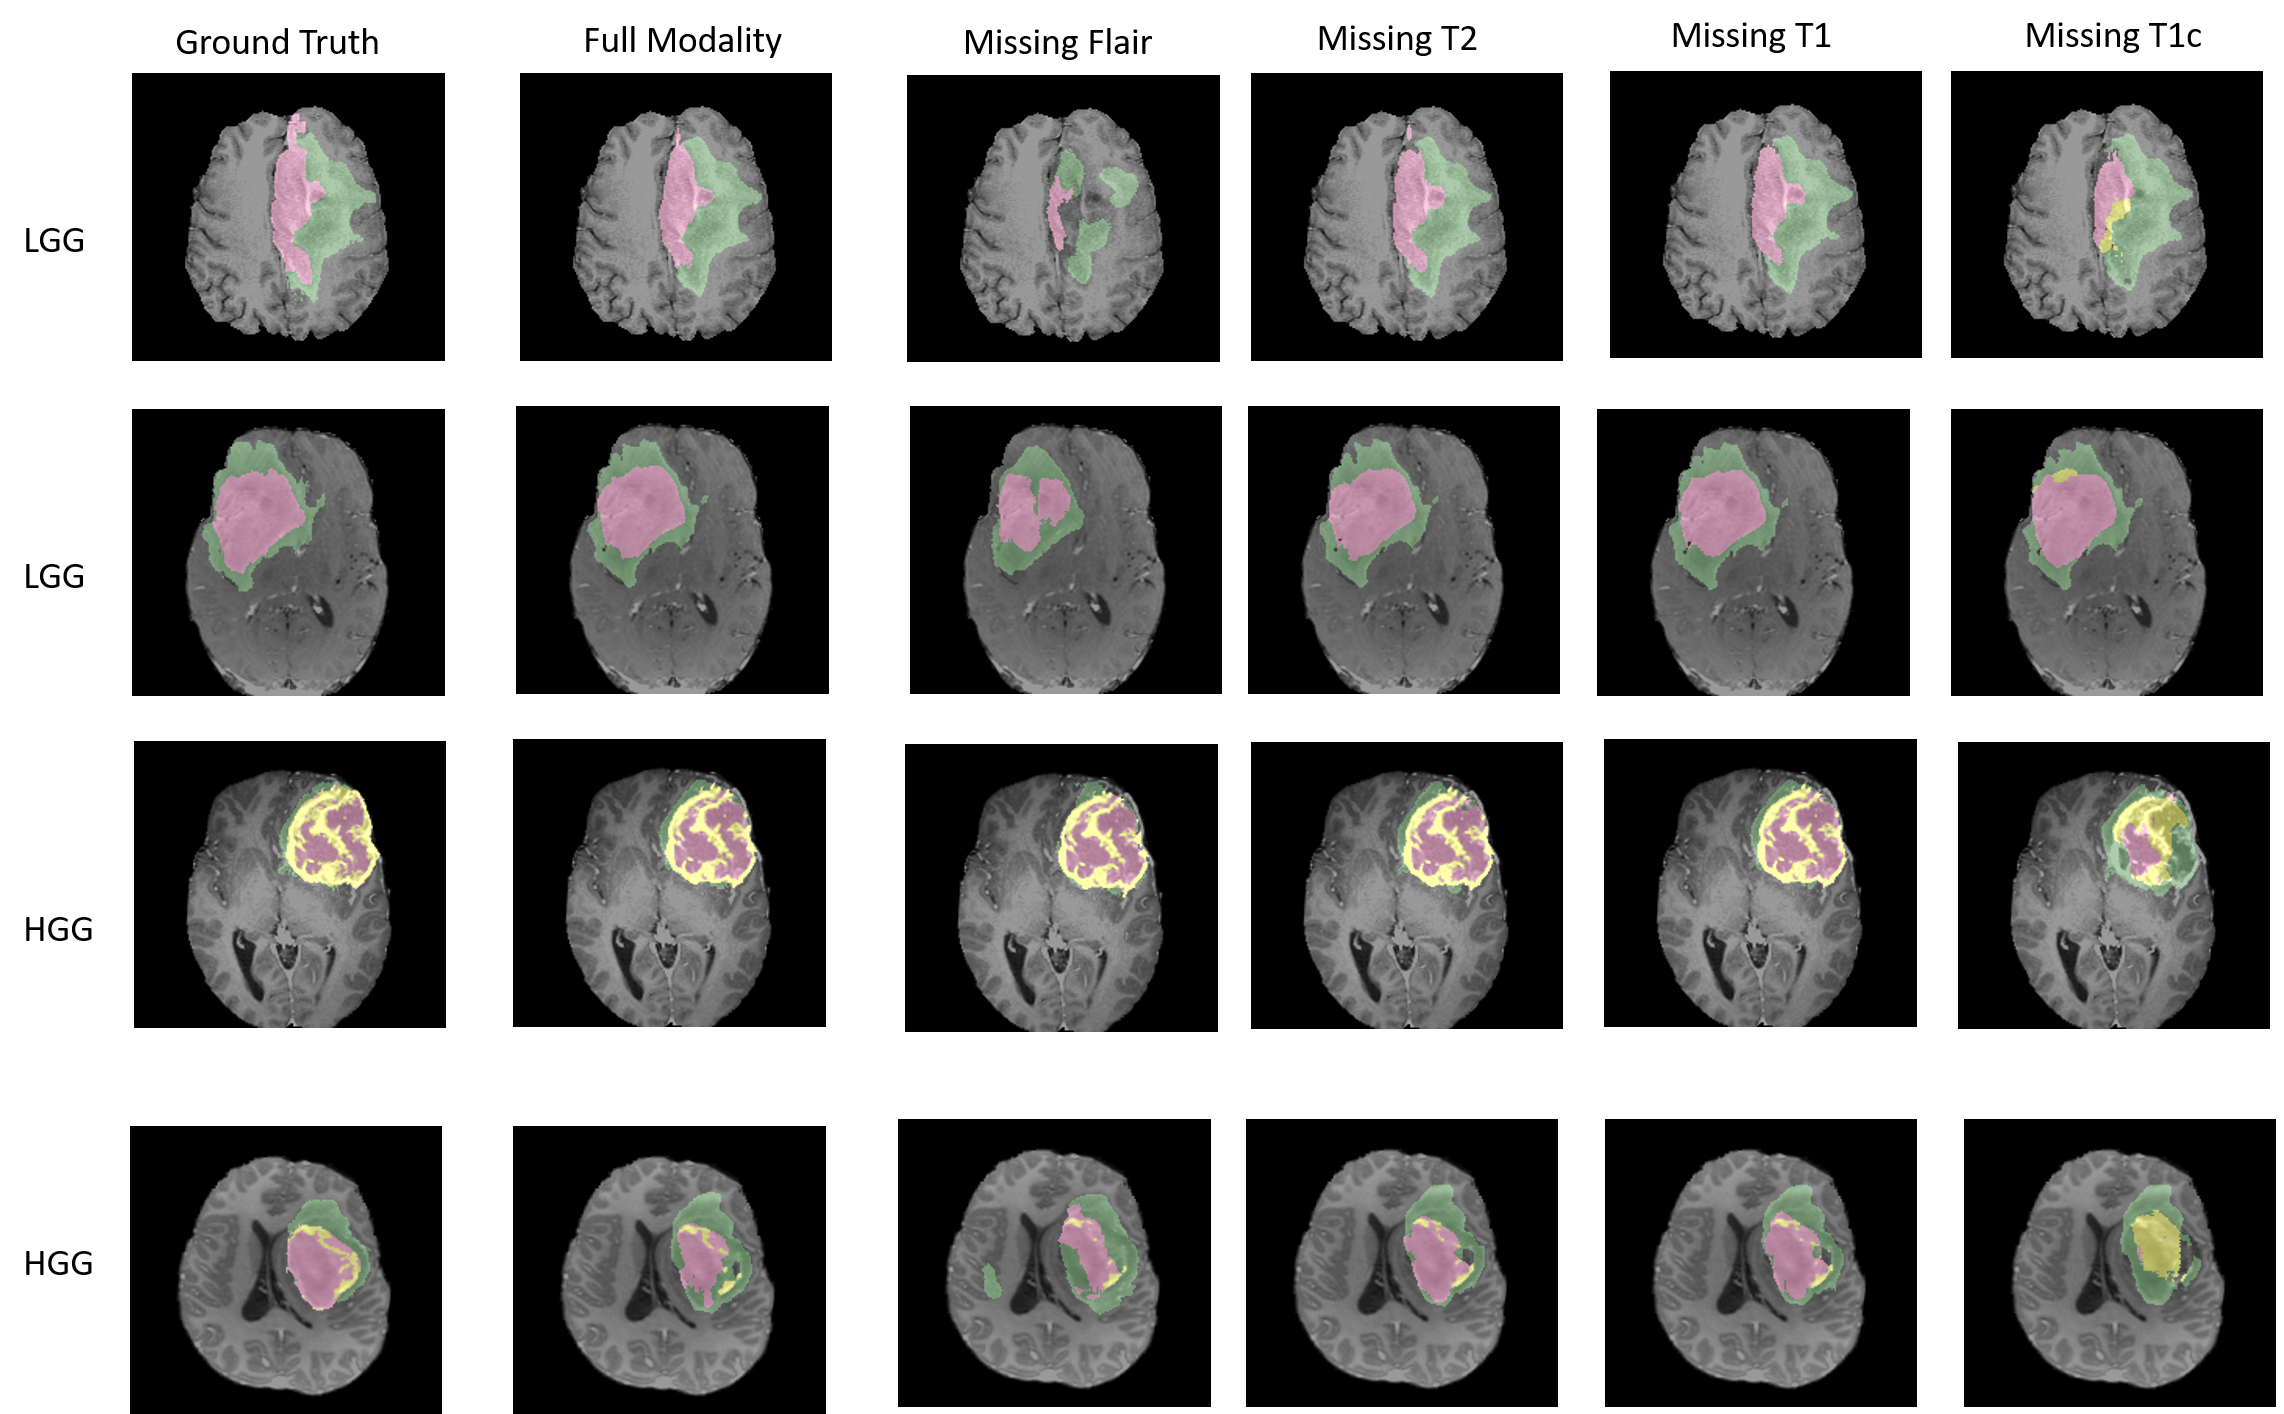

Refer to caption

Figure 3: Examples of the segmentation masks with missing modality compared to the ground truth. The edema area is labeled in green color. The non-enhancing core area is labeled in red color. The enhancing core area is labeled in yellow color.

• As shown in Fig. 3, missing Flair channel would result in a coarse locating on the whole tumor region. And missing T1c channel would result in mistaking tumor core and enhanced core region as non-core region.

To provide justification of domain adaptation loss term we introduce, we also provide an ablation experiment by training only on reconstruction loss in training process. Our baseline result is shown in Table 1. Distinct increases of Dice score in all categories are observed when trained with domain adaptation loss compared with the baseline. The qualitative visualization are consistent with the quantitative results as shown in Fig. 3.